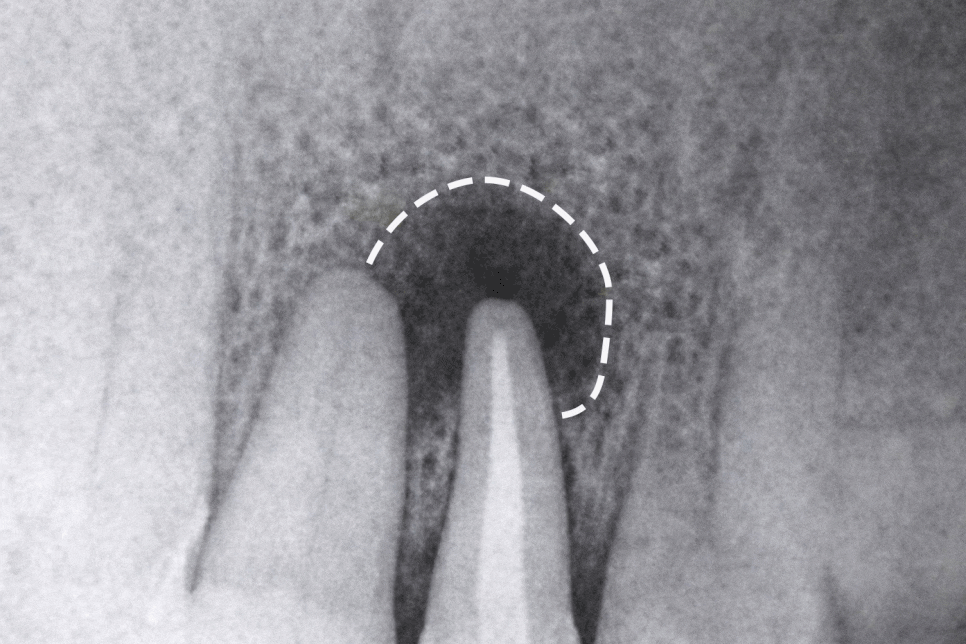

제일 흔한 경우는 치근단 염증으로,

치근단이란 치아 뿌리의 끝 부분을 말하는데

여기에 염증이 생기면 잇몸이 붓거나

통증이 일어날 수 있습니다.

치근단 염증은 시간이 흐르면서

범위가 점점 넓어지는 경우가 많기 때문에

통증이 크지 않다 해서 방치하는 것은

바람직하지 못합니다.

엑스레이 촬영을 통해 치근단 병소가 확인된다면